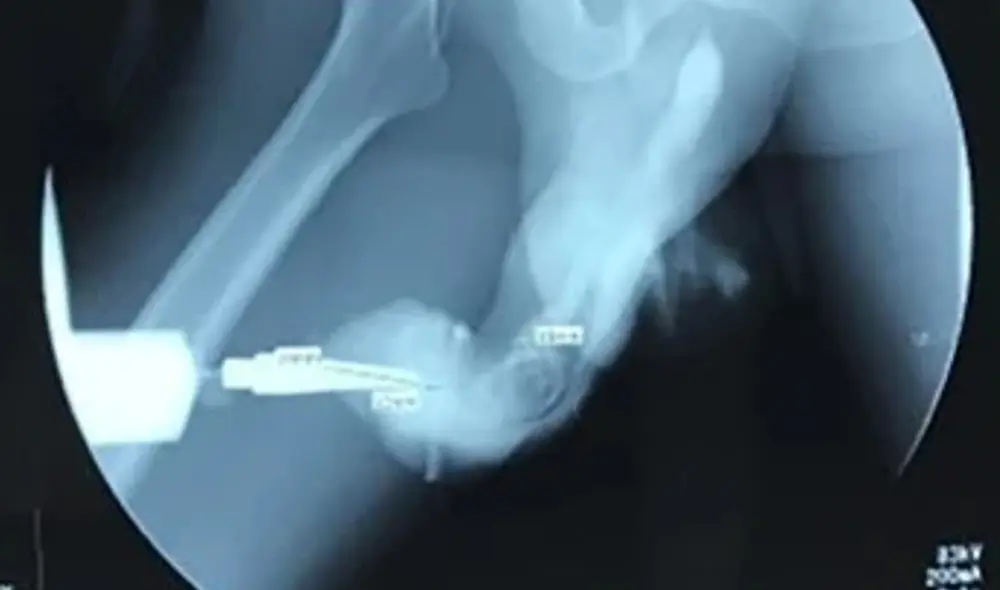

Examen de contraste para ubicar lesiones en el miembro viril. Foto: Clarin

Uno de los exámenes que se le realizó reveló que su miembro viril se había puesto de color dorado y tenía una clara desviación hacia la derecha, parecido a un signo de interrogación. Dicha forma fue corroborada con las radiografías.

Radiografía que muestra la fractura del pene del hombre indonesio. Foto: Clarin